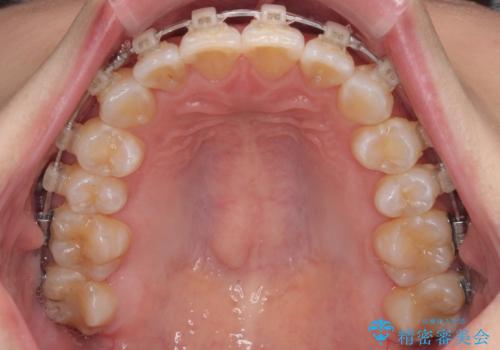

- 審美装置

なかなか舌の突出癖が改善できず、上下前歯が非接触となる期間が長く続きました。

アンカースクリューの活用と、舌のトレーニングを何度も指導し、出っ歯になることなく無事に治療を終えることができました。